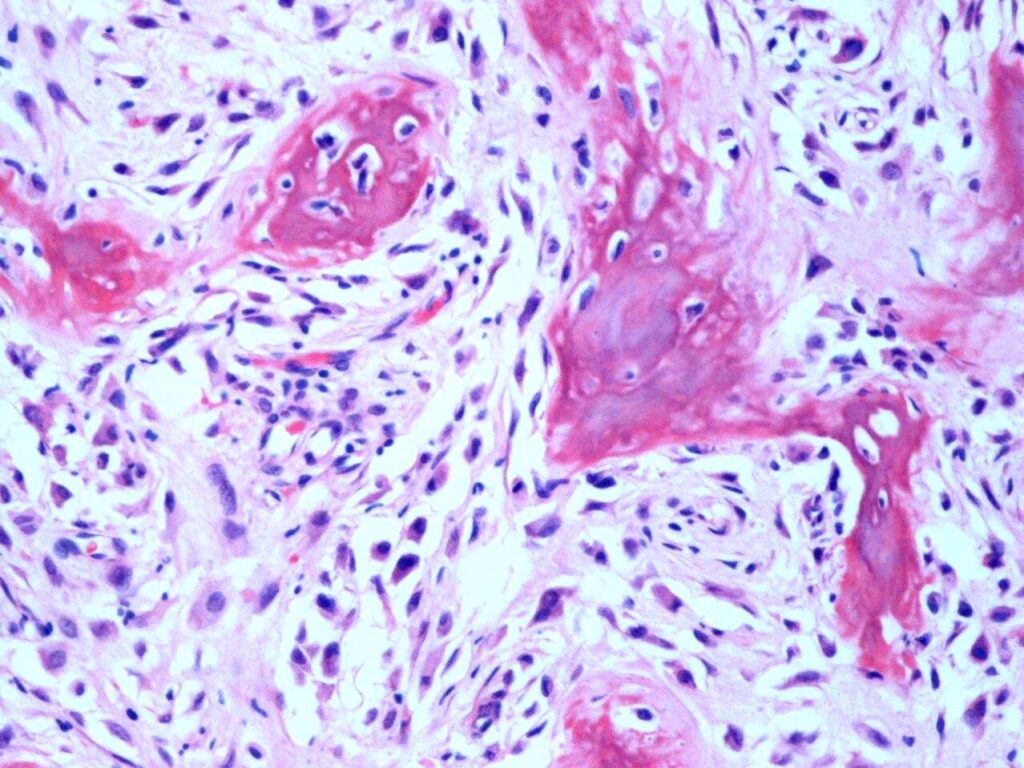

Microscopic

• Display bundles of spindle cell proliferations with variable osteoid production, low cellularity, low mitotic rate, and minimal pleomorphism (Fig. 9 & 10).

• The presence of infiltrative margins and the absence of marked cellular atypia helps to differentiate low grade intraosseous osteosarcoma from benign entities.

Fig. 9 & 10: Microscopic Pathology. Low and high power views with irregular woven bone trabeculae in a moderately cellular fibrous tissue. Atypical cells displaying hyperchromatic nuclei are closely associated with the irregular woven bone trabeculae.